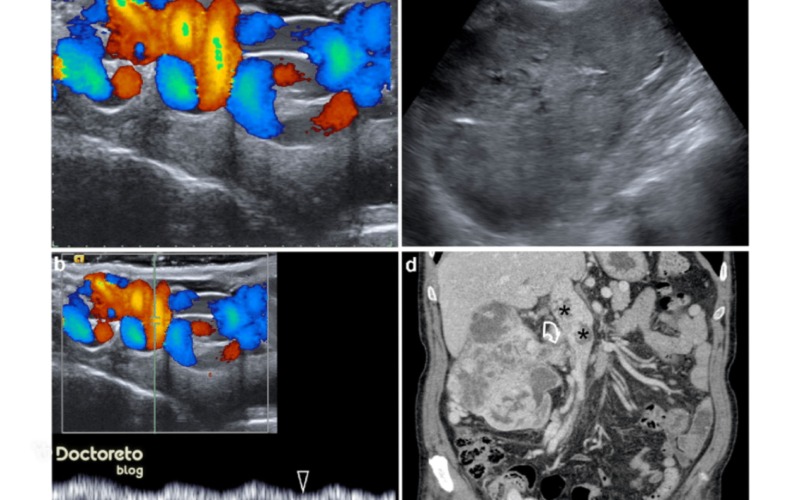

تصاویر واریکوسل

تصاویر سونوگرافی واریکوسل وریدهای پیچخورده و گشاد را نشان میدهد که جریان خون معکوس را برجسته میکند. این تصاویر برای تشخیص دقیق استفاده میشوند و معمولا سیاه و سفید هستند.